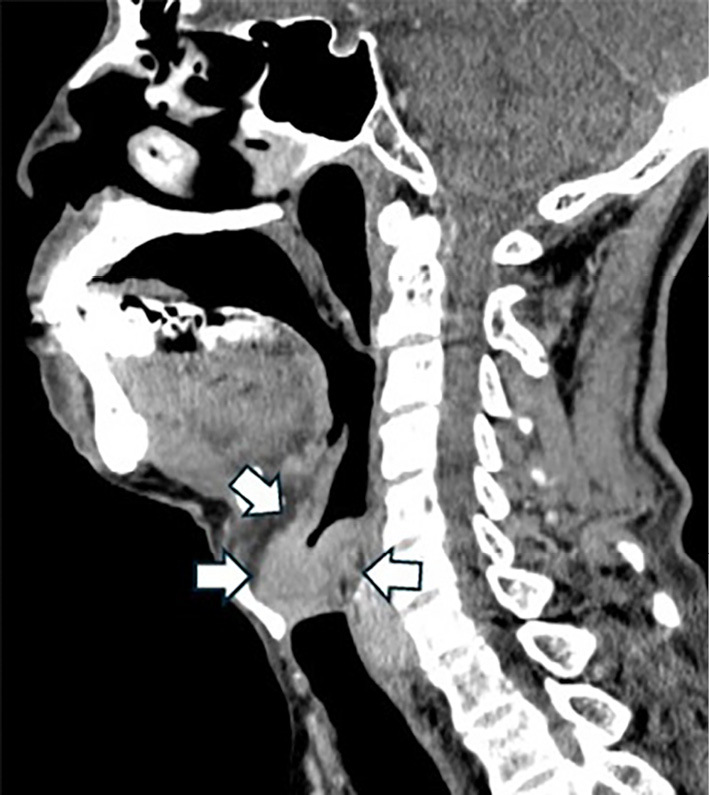

Immune-related Adverse Event Laryngitis in Durvalumab-treated Hilar Cholangiocarcinoma.

杜伐单抗治疗肝门胆管癌的免疫相关不良事件喉炎。